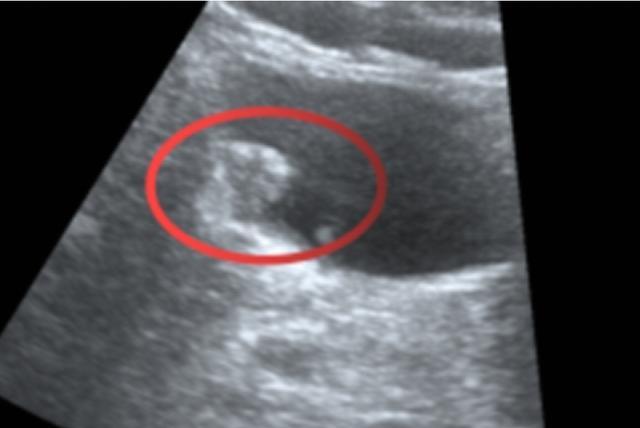

泌尿系超声结果显示:

(▲超声所见:膀胱壁可见大小约12×9mm低回声结节,形态欠规则,改变体位不移动)

超声诊断意见:膀胱壁占位性病变,建议进一步检查。